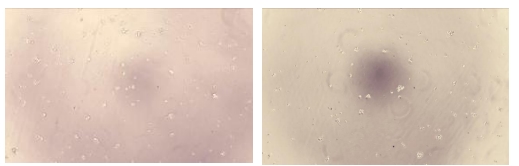

Bio-activity : Interleukin 1 alpha (IL1α) also known as hematopoietin 1 is a cytokine of the interleukin 1 family that in humans is encoded by the IL1A gene. IL1α is produced mainly by activated macrophages, as well as neutrophils, epithelial cells, and endothelial cells. It possesses metabolic, physiological, haematopoietic activities, and plays one of the central roles in the regulation of the immune responses. It binds to the interleukin-1 receptor. It is on the pathway that activates tumor necrosis factor-alpha. To test the effect of IL1a on cell proliferation, Jurkat cells were seeded into triplicate wells of 96-well plates at a density of 2,000 cells/well with 2% serum standard 1640 including various concentrations of recombinant human IL1a. After incubated for 96h, cells were observed by inverted microscope and cell proliferation was measured by Cell Counting Kit-8 (CCK-8). Briefly, 10µL of CCK-8 solution was added to each well of the plate, then the absorbance at 450nm was measured using a microplate reader after incubating the plate for 1-4 hours at 37°C. Proliferation of Jurkat cells after incubation with IL1a for 96h observed by inverted microscope was shown. Cell viability was assessed by CCK-8 (Cell Counting Kit-8) assay after incubation with recombinant IL1a for 96h. It was obvious that IL1a significantly increased cell viability of Jurkat cells.